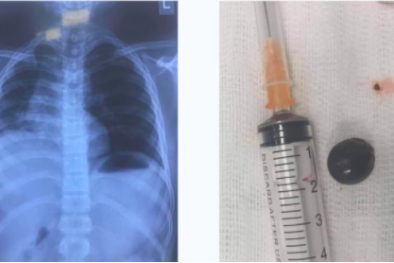

Hạt nhãn rơi vào đường thở trong lúc trẻ vừa chơi đùa vừa ăn gây tức ngực, khó thở

(VietQ.vn) - Bệnh viện Sản nhi Nghệ An cho biết, mùa hè có rất nhiều trẻ bị hóc dị vật nhất là các loại hạt nhãn, hạt vải cha mẹ cần đặc biệt lưu ý.